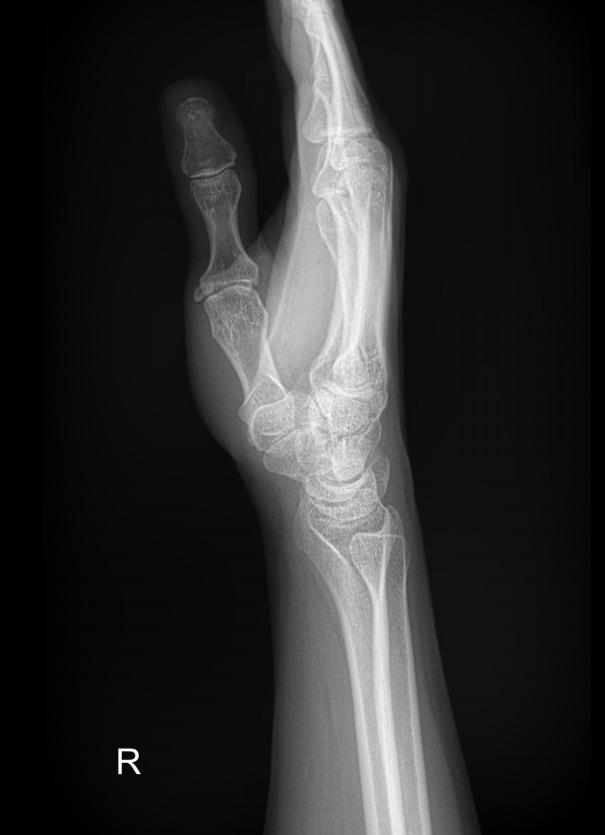

Самым первым исследованием запястья, наряду с лабораторными анализами, обычно является рентген. Это распространенный, простой в проведении и быстрый в получении результатов, а также высоко информативный для всей костной системы метод. В настоящее время он стал и практически безопасным в плане облучения: количество испускаемых лучей минимально и позволяет выполнять рентгенодиагностику несколько раз в год, не набирая при этом максимально допустимой дозы.

Что показывает рентген лучезапястного сустава

• Взаимоотношения суставных поверхностей ― в норме или вывих;

• Состояние суставной щели ― в норме, сужена, есть ли выпот и обызвествление капсулы;

• Состояние суставных поверхностей ― эрозии или ровный контур;

• Структура костной ткани ― типична, остеопения, деструкция или другие патологии;

• Переломы, трещины, костные обломки;

• Изменения в мягких тканях;

• Новообразования.

О других проекциях ― боковой, косых и специальных для исследования отдельных костей ― лечащий врач дополнительно пишет в направлении.